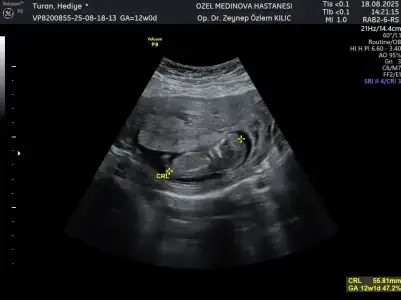

Banada tahminde bulunabilir misiniz? Kendi doktorum erkeğe benziyor başka bir doktor kıza benzettiği söyledi

Dojtorunuz ölçüm çizgisini hep cinsiyet kısmına denk getiriyor, yine aynı olmuş 🤦🏻‍♀